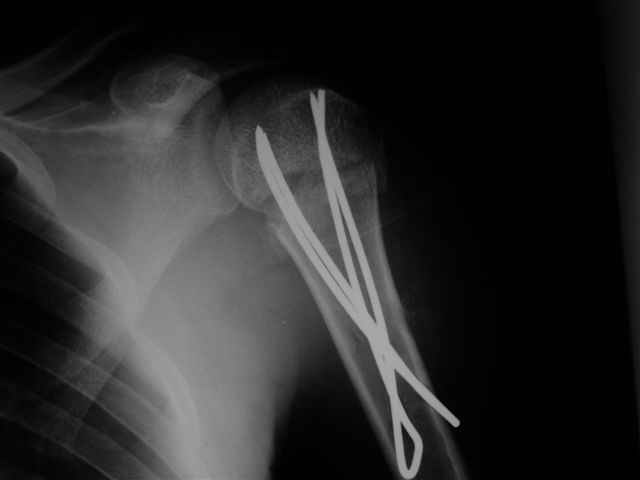

Посылаю послеоперационные Рг граммы.

Я и сам доволен результатом. В предпоследнем письме я кратко описал ход операции - закрыто репонировать не удалось( 2 недели с момента травмы и 1 неделя после неудачной репозиции) после удаления пучков спиц, пришлось сделать - 2см разрез на уровне перелома и с помощью периостального элеватора (золотое правило механики) *одеть* головку на дистальный отломок.

Спицы проводил через старые отверстия, вращая пучок импактором- направителем при его введении в головку.